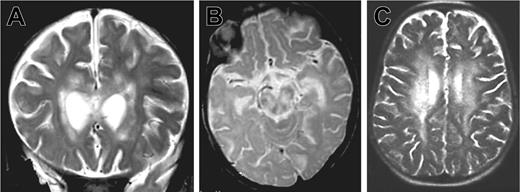

Patient 1 was the third child of consanguineous parents from Algeria. There was no known family history of neurologic disease or early death. Three other siblings were healthy. The patient was hypotrophic at birth (weight 2300 g, length 47 cm, and head circumference 30 cm at 39 weeks gestation). Neurologic symptoms were first noted at 5 months of age after an acute and apparently benign upper respiratory infection: poor head control, tremor of extremities, and abnormal postural tone for age. The patient was hospitalized 2 months later because of the onset of seizures, status epilepticus, ataxia, and coma without fever. Within 2 weeks, the patient developed persistent myoclonus, pyramidal rigidity of lower limbs, right facial weakness, and impaired ocular movements. Two brain magnetic resonance imagings (MRIs) were performed 3 weeks apart at the age of 8 months. Large areas of white matter at periventricular, deep supratentorial, and cerebellar locations were hyperintense in relaxation time (T) 2-weighted and fluid-attenuated inversion recovery (FLAIR) images and hypointense on T1-weighted images and showed contrast enhancement after application of gadolinium (Figure 1A-B). There was also evidence of lesions in the corpus callosum and brain stem mostly in the tegmentum and the pons. No subcortical, cortical, or basal ganglia abnormalities were detected. Lesions were larger on the second MRI. In addition, a moderate degree of hepatosplenomegaly and a 5-cm right cervical mass were detected.

Brain magnetic resonance images of patients 1 and 2. MRIs show large white matter lesions in periventricular areas and brain stem. (A) Patient 1, 7 months, coronal T2 section. (B) Patient 1, 7 months, sagittal T2 section. (C) Patient 2, 33 months, sagittal T2 section.

Three months later (33 months of age), patient 2 was admitted to our hospital with fever, weight loss, and anorexia. Clinical examination revealed massive hepatosplenomegaly. The results of laboratory investigations are shown in Table 1. Severe pancytopenia and a high percentage of HLA DR(+) CD4 and CD8 lymphocytes were observed. In addition, hypertriglyceridemia, hyponatremia, and lymphocytic meningitis were found. Transaminase, fibrinogen, and ferritin levels remained normal. Hemophagocytosis was observed on a bone marrow aspirate. Infection by herpes simplex viruses (HSVA-C), human herpes virus 6 (HHV6), cytomegalovirus (CMV), human immunodeficiency virus (HIV), adenovirus, bacteria, and fungi were excluded. Low copy number of EBV (0.8 log) was detected by PCR in the blood. CSF cultures were negative for bacteria and fungi. A normal level of interferon α (IFN-α; < 2 IU) was detected in the CSF, making viral infection highly unlikely. CSF lactate level was elevated. Treatment consisted of steroids and cyclosporine A (CsA). In 6 days, the hepatosplenomegaly, fever, and biomarkers of disease activity completely regressed, but on the seventh day, an acute neurologic deterioration occurred with coma and choreoathetoid movements. An MRI was performed, showing an extension of the lesions (Figure 1C).

These 2 cases illustrate that the initial signs of FHL can present as a chronic encephalitis of subacute onset, which can precede systemic manifestations by several months or even years. Although primarily CNS findings have already been reported in FHL,6,7,19 or in EBV-induced hemophagocytic syndrome,20 the cases described here are the first ones molecularly characterized with such early onset of the neurologic symptoms and long delay between the onset of the neurologic symptoms and first clinical signs of systemic illness (ie, 27 months in patient 2). Of note, limited focal necrosis and parenchymal volume loss were observed in these cases compared with classical perforin-deficient FHL patients with neurologic involvement.4,9 Both patients had an elevated CNS lactate concentration, which could have led to an erroneous diagnosis of metabolic disease at that age.